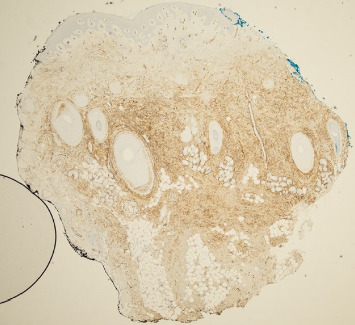

Dermatofibrosarcoma protuberans (DFSP) is a rare, slow-growing soft tissue tumor affecting the dermis and subcutaneous tissues, with potential involvement of muscle and fascia. This case report describes a 68-year-old Caucasian male with a history of recurrent DFSP on the left cheek, initially excised 36 years ago, with multiple recurrences despite wide local excisions (WLEs), eventually requiring left orbital enucleation, presenting to the clinic with a 10-year history of a slow-growing lesion on the left temporal scalp. Examination revealed a 2 cm flesh-colored, firm nodule, which biopsy confirmed as DFSP. Despite two subsequent WLEs, positive margins persisted. The patient refused further surgical intervention and was referred for imatinib and radiation therapy, which he also declined. MRI revealed additional nodules near the left zygomatic arch and sternocleidomastoid. DFSP is diagnosed via biopsy, often confirmed with CD34 immunohistochemistry. Optimal treatment is Mohs micrographic surgery (MMS), but WLE is also used. The recurrence rate is high, especially in head and neck locations. This case underscores the necessity for multidisciplinary management and highlights the critical role of thorough physical and histopathologic examinations. Close clinical follow-up is essential due to the high recurrence risk within the first three years post-treatment. This report emphasizes the importance of early detection and comprehensive care strategies to manage DFSP effectively.